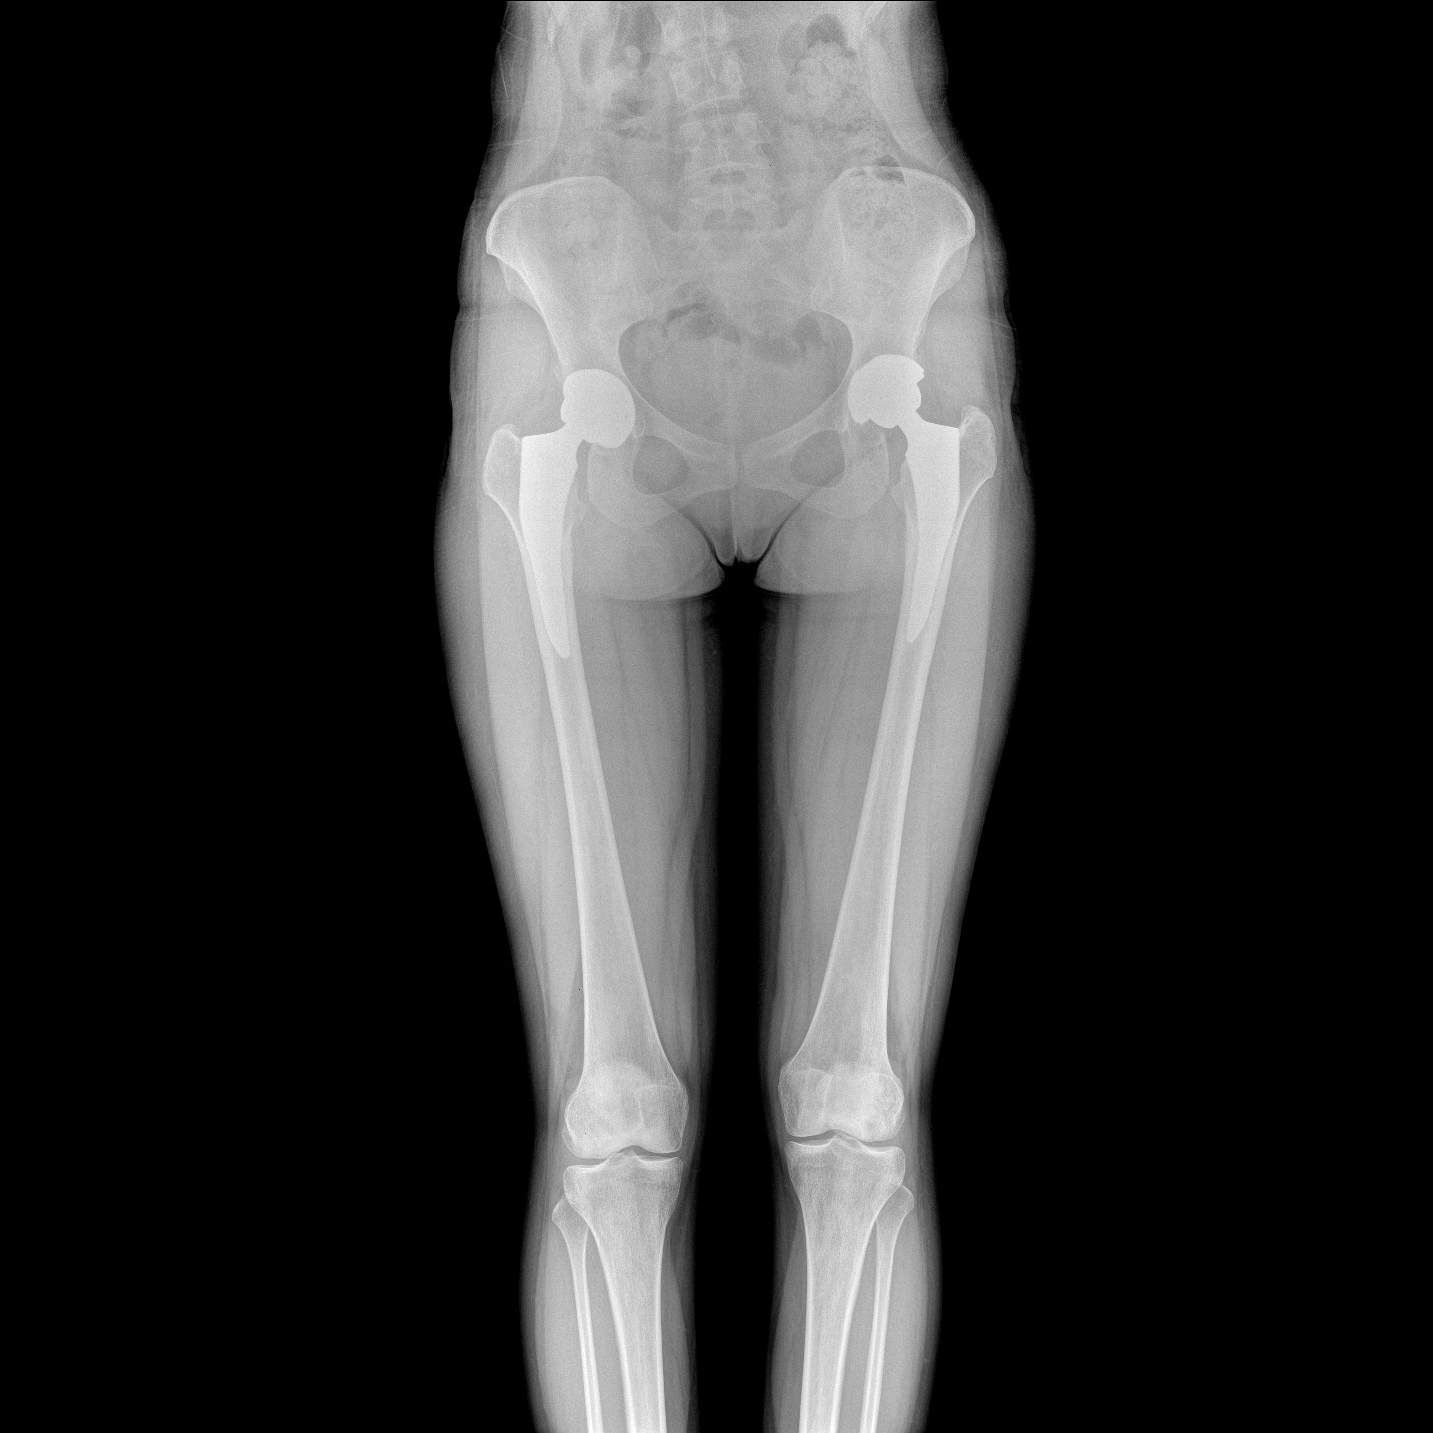

支持全脊柱攝影、雙下肢攝影、脊髓造影、復雜創(chuàng)傷、人工關(guān)節(jié)置換、關(guān)節(jié)損傷的修復重建等大視野臨床應用

17"*34"有效視野,一次成像不拼接。相較于多張攝影再軟件拼接的DR設備,PLX8600解決了拼接圖像存在密度不均勻,拼接處圖像配準和放大效應等問題,給臨床帶來了大視野影像解決方案,可一次性覆蓋全脊柱或雙下肢影像。